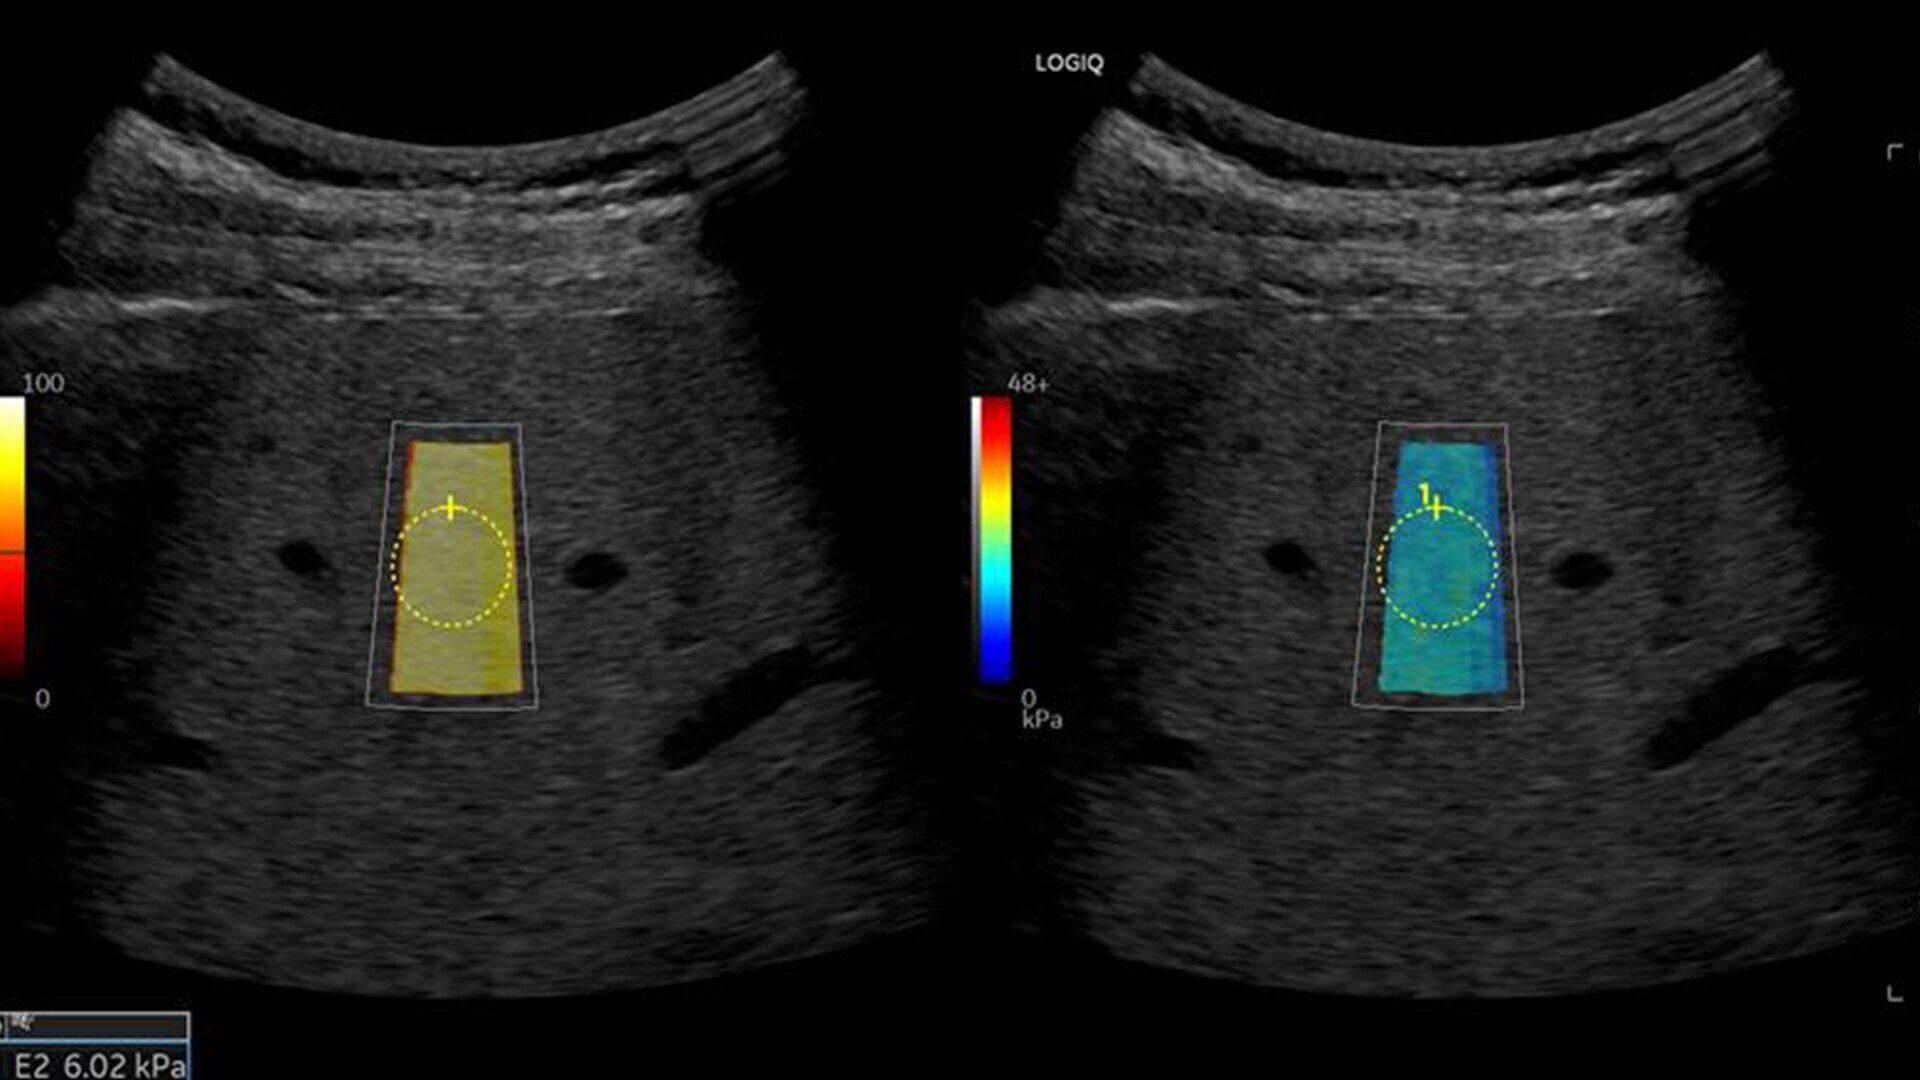

• 2D shear wave elastography with quality map provides quantitative insight into tissue elasticity—helping you assess different structures with confidence

• Hepatic Assistant: Combines 2D shear wave elastography and UGFF in a single workflow